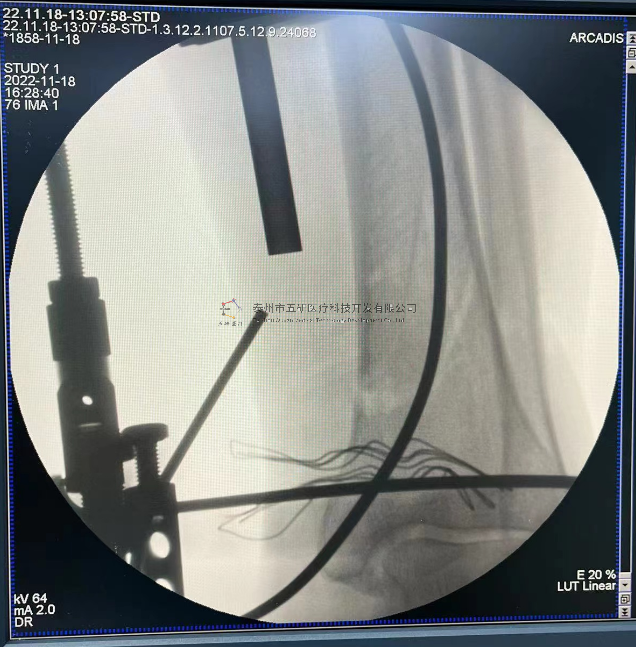

// 下肢骨折

【所屬科室】中國(guó)中醫(yī)科學(xué)院望京醫(yī)院創(chuàng)一科

【基本資料】患者,男,65歲

【患者情況】脛骨遠(yuǎn)端骨折伴腓骨骨折

【影像圖片—術(shù)后】